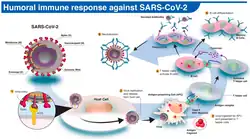

El ARN del virus SARS-CoV-2 codifica 4 proteínas estructurales: la proteína S (spike protein), la proteína E (envelope), la proteína M (membrane) y la proteína N (nucleocapsid). La proteína N está en el interior del virión asociada al RNA viral, y las otras cuatro proteínas están asociadas a la envoltura viral. La proteína S se ensambla en homotrímeros, y forma estructuras que sobresalen de la envoltura del virus. La proteína S contienen el dominio de unión al receptor celular y por lo tanto es la proteína determinante del tropismo del virus y además es la proteína que tiene la actividad de fusión de la membrana viral con la celular y de esta manera permite liberar el genoma viral en el interior de la célula que va a infectar.[97]

El SARS-CoV-2 penetra en la célula empleando como receptor a la enzima convertidora de angiotensina 2 (ACE-2 por sus siglas en inglés), una exopeptidasa de membrana presente fundamentalmente en el riñón, los pulmones y el corazón.[98] Se ha observado que los casos graves de COVID-19 presentan niveles de Angiotensina II muy altos. Y el nivel de angiotensina II se ha correlacionado con la carga viral de SARS-CoV-2 y el daño pulmonar. Este desequilibrio del sistema renina-angiotensina-aldosterona podría estar en relación con la inhibición de la enzima convertidora de angiotensina-2 por parte del virus. Este mismo mecanismo fue observado en el brote producido por síndrome respiratorio agudo grave en 2003.[97]

La glicoproteína S de la envoltura del virus interacciona con el receptor celular ECA2 (enzima convertidora de angiotensina 2), una proteína de la membrana celular que cataliza la conversión de angiotensia I en el nonapéptido angiotensina 1-9 o de angiotensia II en angiotensina 1-7. El virus entra por endocitosis. Una vez en el endosoma ocurre una bajada de pH mediada por lisosomas, que promueve la fusión de la membrana del endosoma con la envoltura del virus, lo que libera la nucleocápside al citoplasma. Proteasas celulares degradan la cápside y el genoma del virus queda libre en el citoplasma. A continuación, al ser un genoma ARN sentido positivo, la maquinaria celular traduce directamente a poliproteínas que son procesadas y se forma el complejo de replicación y transcripción. Luego se sintetiza la hebra complementaria de ARN pre-genómico sentido negativo que servirá como molde para replicar el genoma viral sentido positivo. Además, el complejo de replicación y transcripción sintetizará a una serie de ARN subgenómicos sentido positivo, más pequeños. Estos son los que se traducirán a las proteínas virales. Todo este proceso ocurrirá en el citoplasma de la célula. Se irán sintetizando las proteínas estructurales que se expresarán en la membrana del retículo endoplasmático. Ahí, en el retículo, es donde ocurrirá el ensamblaje. De hecho la envoltura del virus proviene de la membrana del retículo endoplasmático. La partícula viral viajará, a través del sistema de transporte de vesículas celular en el que interviene el aparato de Golgi, hasta la superficie. La partícula viral saldrá de la célula por exocitosis. Tras una última fase de maduración, en la que intervienen proteasas virales, todos los componentes del virus encajarán, la partícula será infecciosa y podrá comenzar un nuevo ciclo celular.[99]

El virus puede pasar a través de las mucosas, especialmente la mucosa nasal y laríngea, luego ingresa a los pulmones a través del tracto respiratorio. Entonces el virus atacaría a los órganos objetivo que expresan ECA2, como los pulmones, el corazón, el sistema renal y tracto gastrointestinal. El virus comienza un segundo ataque, causando que la condición del paciente empeorar alrededor de 7 a 14 días después del inicio. La reducción de linfocitos B puede ocurrir temprano en la enfermedad, que puede afectar la producción de anticuerpos en el paciente. Además, los factores inflamatorios asociados con las enfermedades que contienen principalmente IL-6 aumentaron significativamente, lo que también contribuyó al agravamiento de la enfermedad alrededor de 2 a 10 días después del inicio. El espectro clínico de COVID-19 varía de formas asintomáticas[100] a condiciones clínicas caracterizadas por insuficiencia respiratoria severa que requiere ventilación mecánica y apoyo en una unidad de cuidados intensivos (UCI), a manifestaciones en varios órganos y sistemas produciendo sepsis, shock séptico y síndrome de disfunción multiorgánica.[97]

Inmunidad

La respuesta inmunitaria natural de los seres humanos al virus SARS-CoV-2 se produce como una combinación de la inmunidad mediada por células y la producción de anticuerpos, igual que con casi todas las otras infecciones.[143] Las células B interactúan con las células T y comienzan a dividirse antes de la selección en la célula plasmática, en parte sobre la base de su afinidad por el antígeno. La presencia de anticuerpos neutralizantes en la sangre se considera una prueba de inmunidad contra la infección, pero el nivel de anticuerpos neutralizantes disminuye con el tiempo, llegando a desaparecer tras tres meses en el 1% de los pacientes y tras seis meses en el 12%.[144] Sin embargo, la ausencia de anticuerpos en la sangre no significa que el sistema inmunitario no pueda producir nuevos anticuerpos rápidamente en caso de reexposición al SARS-CoV-2. Las células B de memoria específicas para las proteínas de la nucleocápside y el pico del SARS-CoV-2 duran al menos 6 meses después de la aparición de los síntomas.

La inmunidad innata frente al SARS-CoV-2 se utilizan principalmente por macrófagos y Células NK,en la inmunidad celular se utiliza por células dendriticas,linfocitos T CD4+ y linfocito T CD8+, y también en la inmunidad humoral la primera línea de defensa se utiliza la IgM y después la IgG, las citocinas implicadas en la inmunidad es el balance entre proinflamatorio y antiinflamatorio (IL-1β, IL-1RA, IL-2RA, IL-6, IL-7, IL-8, IL-9, IL-10, FGF básico, G-CSF, GM-CSF, HGF, Interferón gamma, IP-10,MCP-1, MIP-1a, MIP-1b,PDGF, TNF-α, VEGF y TGF-beta), la duración es alrededor de 2 semanas.[156][157][158][159] La presencia de algunas variantes en loci de las secuencias del gen del interferón reduce la inmunidad natural y estimula la susceptibilidad a enfermedades virales graves, incluida la COVID-19.[160][161]